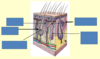

What structures are labelled in the diagram?

What is the role of the sebaceous glands?

they secrete sebum

one type is associated with the hair follicle and secretes sebum into the hair follicle

the other type secretes sebum directly onto the surface of the skin

What is the role of eccrine glands?

they have a thermoregulation function and produce sweat

they are the major sweat glands of the human body that are found in virtually all skin

they have the highest density in the palm and soles and lowest density on the trunk and extremities

What is the role of the apocrine glands?

apocrine glands in the skin and eyelid are sweat glands

most are found in the armpits, groin and area around the nipples

apocrine glands in the skin are scent glands and their secretions usually have an odour

What is the role of the arrector pili muscle?

it is a bundle of smooth muscle fibres

it inserts at one end into the follicle sheath just below the sebaceous glands and the other in the superficial dermis

What is shown in this image?

hair bearing skin